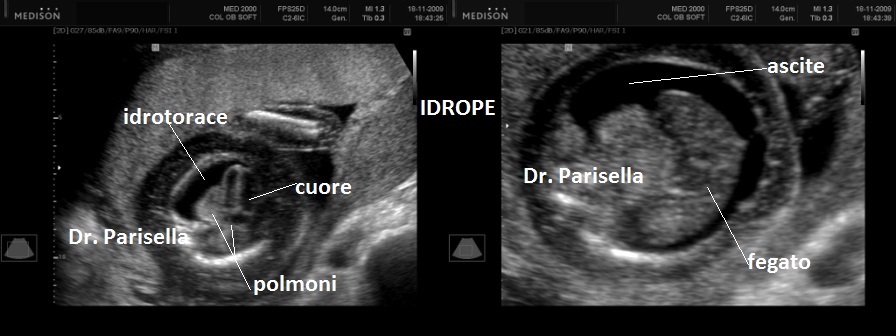

I segni principali sono la micromelia marcata, l'idrope fetale e ossificazioni ectopiche.

2. idrope fetale